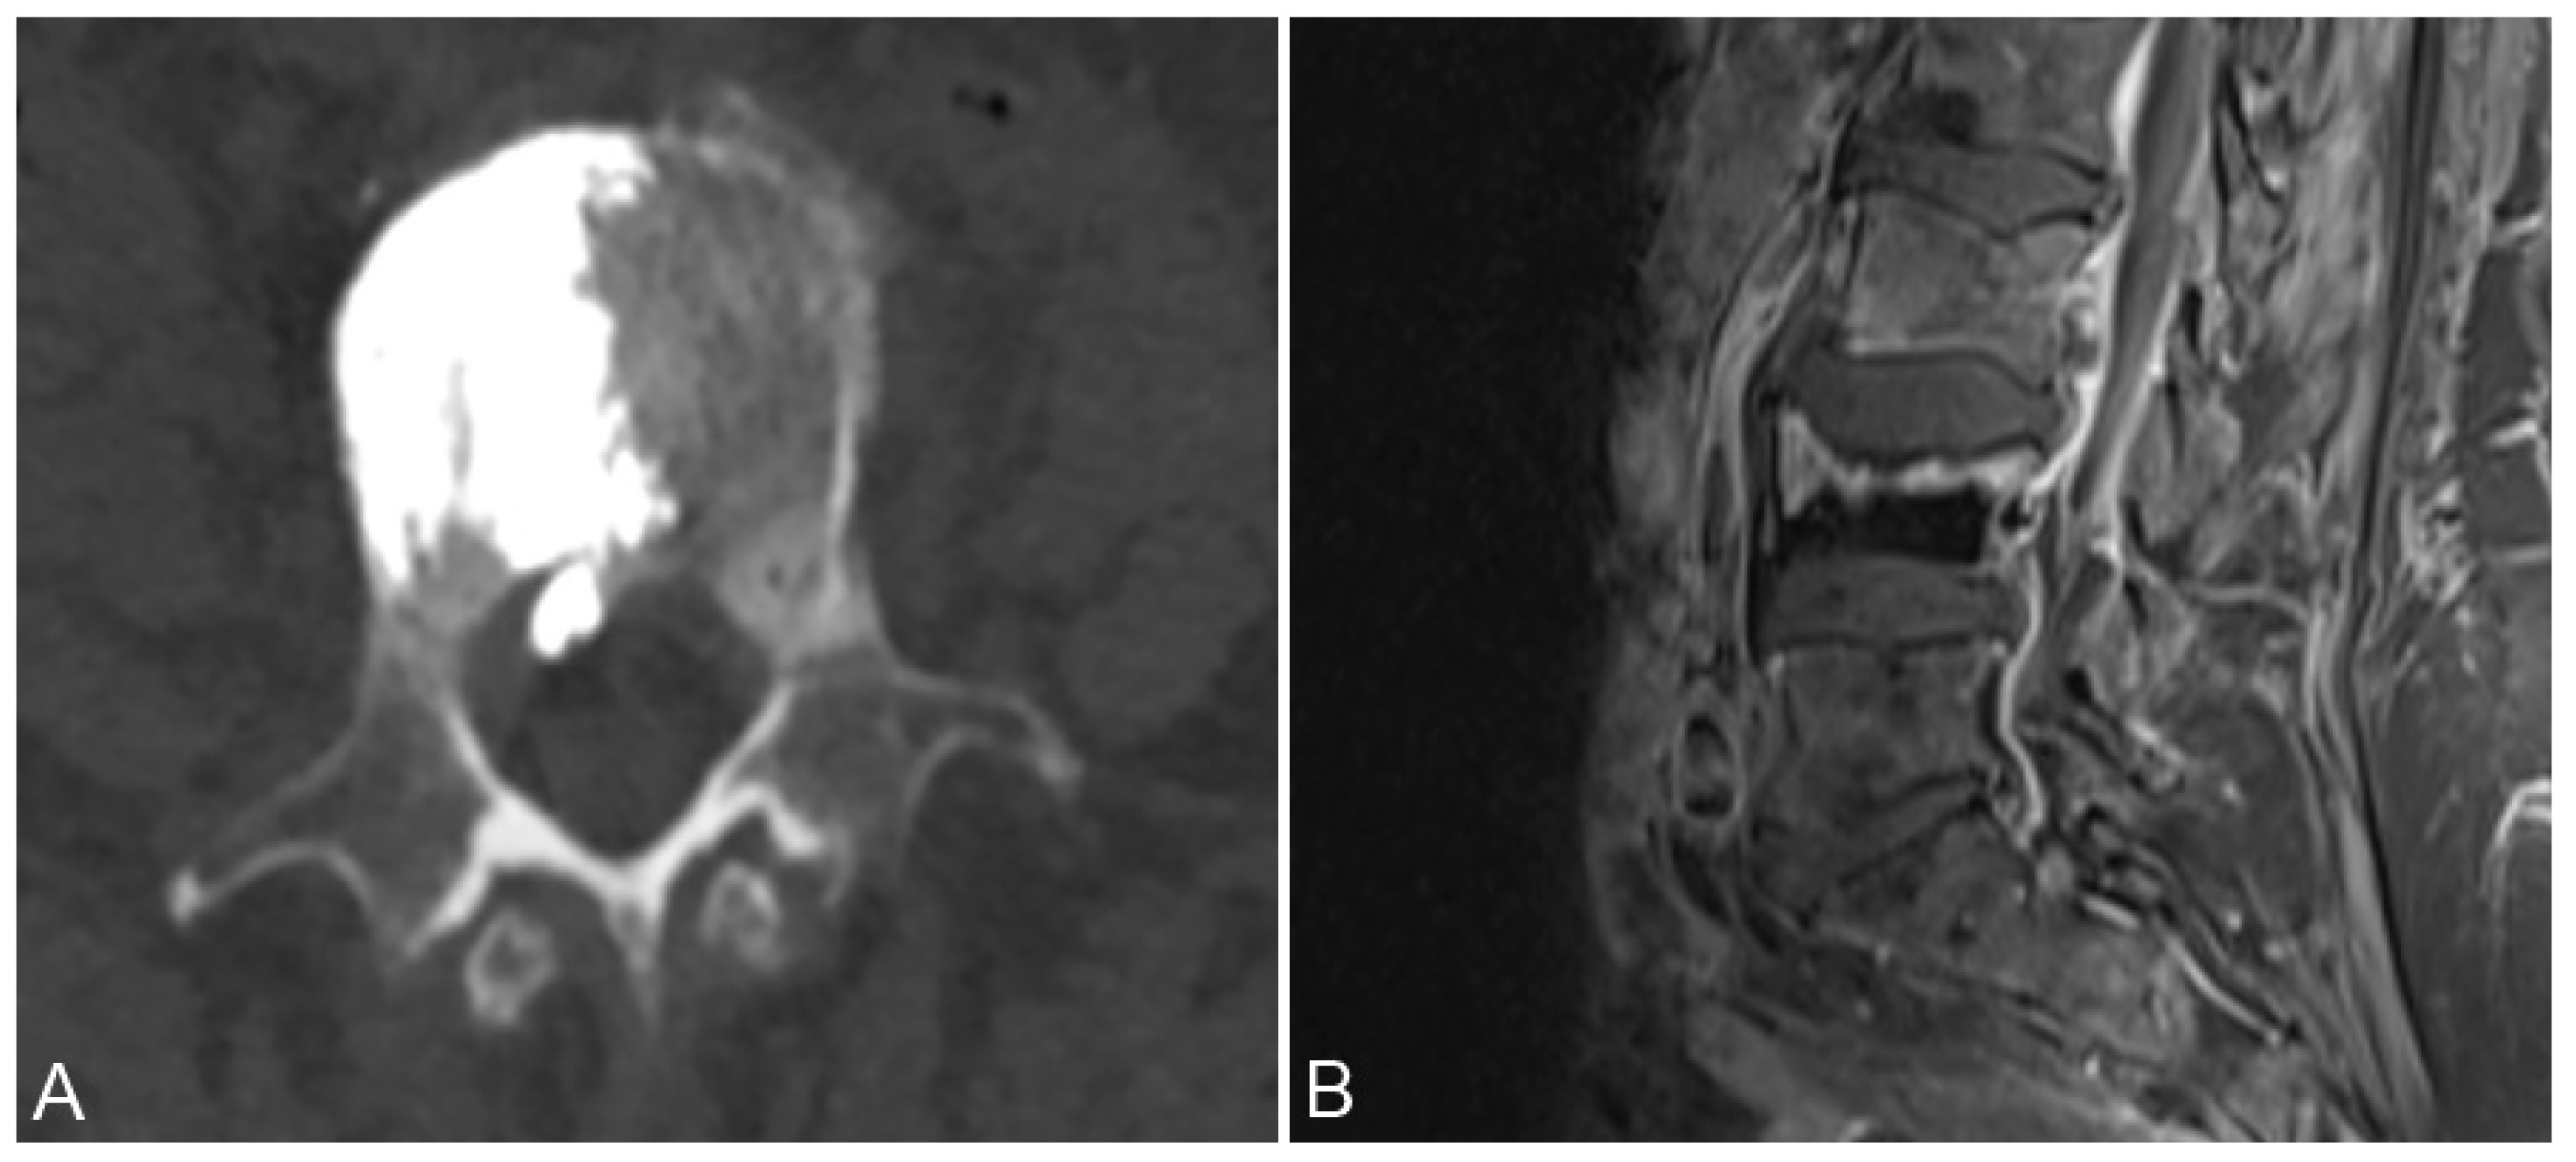

3.3. Paravertebral Soft Tissue Leakage